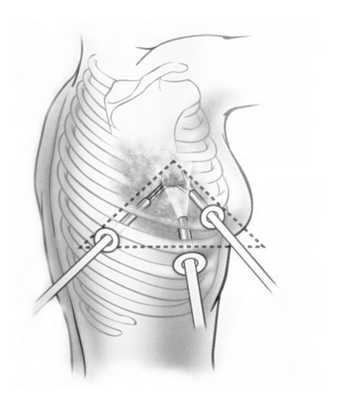

Для осуществления биопсии легкого выполняют 3 разреза в форме треугольника, а при необходимости еще один разрез, для последующего введения дренажной трубки